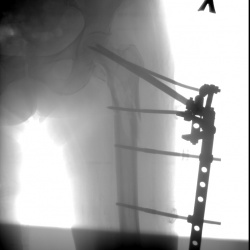

Перелом и подвыв головки плечевой кости? М 55 лет. Упало 3 дня назад подозрение на перелом головки плечевой кости. Головка поднята доверху, есть ли подвивы или перелом?